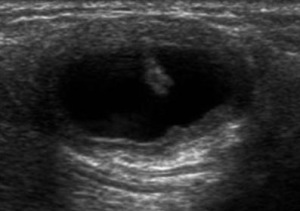

Цистицеркоз диагностируют при помощи УЗИ, рентгена, КТ, МРТ и биопсии. На УЗИ хорошо видно кисту и сколекс цистицерка в мышцах и подкожной клетчатке. На рентгене видно кальцификаты. КТ и МРТ полезны для определения точного расположения цистицерка. На КТ лучше видны мелкие кальцинаты. На МРТ лучше видно сколекс и кисту.

| Фото. Цистицерки в мышцах на УЗИ. А, Б У ребенка безболезненная припухлость в правом подреберье. На УЗИ очаг (16,5х7,5 мм) с кистозным компонентом (6,3х4 мм) и гиперэхогенным (белым) включением внутри (стрелка). Диагноз цистицеркоз передней брюшной стенки. В цистицерк в икроножной мышце. | ||